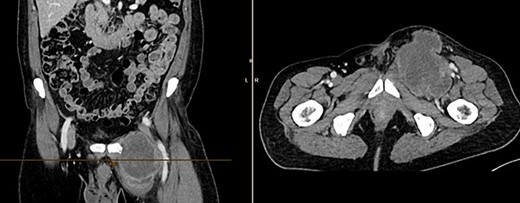

Further clarification was sought through a computed tomography (CT) scan of the entire abdomen (Fig. 1). The CT from 25 February 2022 showed an oval, encapsulated structure in the right groin area, most likely interpreted as a soft tissue hematoma. No active bleeding was observed. An enlarged lymph node was considered as a differential diagnosis. A follow-up CT on 1 August 2022 showed a size-progressive formation within the suspected right inguinal hernia compared with the previous examination in February (Fig. 2). There was no evidence of tumor recurrence or metastasis-suspect lesions intra-abdominally. A previous hysterectomy was also noted.

CT of the abdomen from 1 August 2022: size-progressive formation within the right inguinal hernia compared with the previous examination from 25 February 2022; no indication of tumor recurrence or metastasis-suspect lesions intra-abdominally, post-hysterectomy.